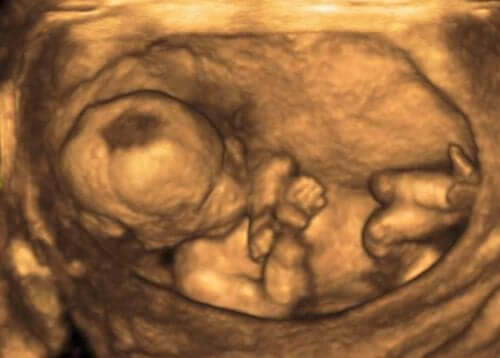

Essas alterações geralmente são detectadas por meio da medição do volume de líquido amniótico no ultrassom. Essa medição é realizada por meio do Índice de Líquido Amniótico ou ILA. Para obter esses dados, o útero é dividido em quatro quadrantes e as áreas livres do feto e do cordão umbilical são medidas em centímetros verticais. Um ILA é considerado normal quando está entre 8 e 21 cm.